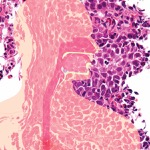

There are many challenges in the diagnosis of EoE, Dr. Smadi noted. They include patchy distribution of eosinophils increasing miss rates for biopsies and high rates of eosinophil degradation, leading to problems with hematoxylin and eosin staining. When biopsies do not provide a definitive diagnosis, it can lead to delayed or inappropriate care.

Based on a previous study establishing EDN as a biomarker for EoE, elevated EDN was defined as a value higher than 10 mcg/nL (Dis Esophagus 2018;31[12]:12). Active EoE was defined as PEC of at least 15 cells per high-power field.